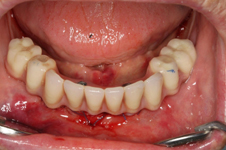

V případě chybění většího počtu zubů v postranních úsecích čelistí je možné ošetření pomocí implantátů, které nahradí ošetření pomocí snímacích náhrad kotvených na zbývajících zubech nebo patře.

Podmínkou je opět dostatečné množství kosti.

Protetické řešení může být pomocí můstku, který je kotvený na implantátech nebo pomocí jednotlivých korunek na implantátech.